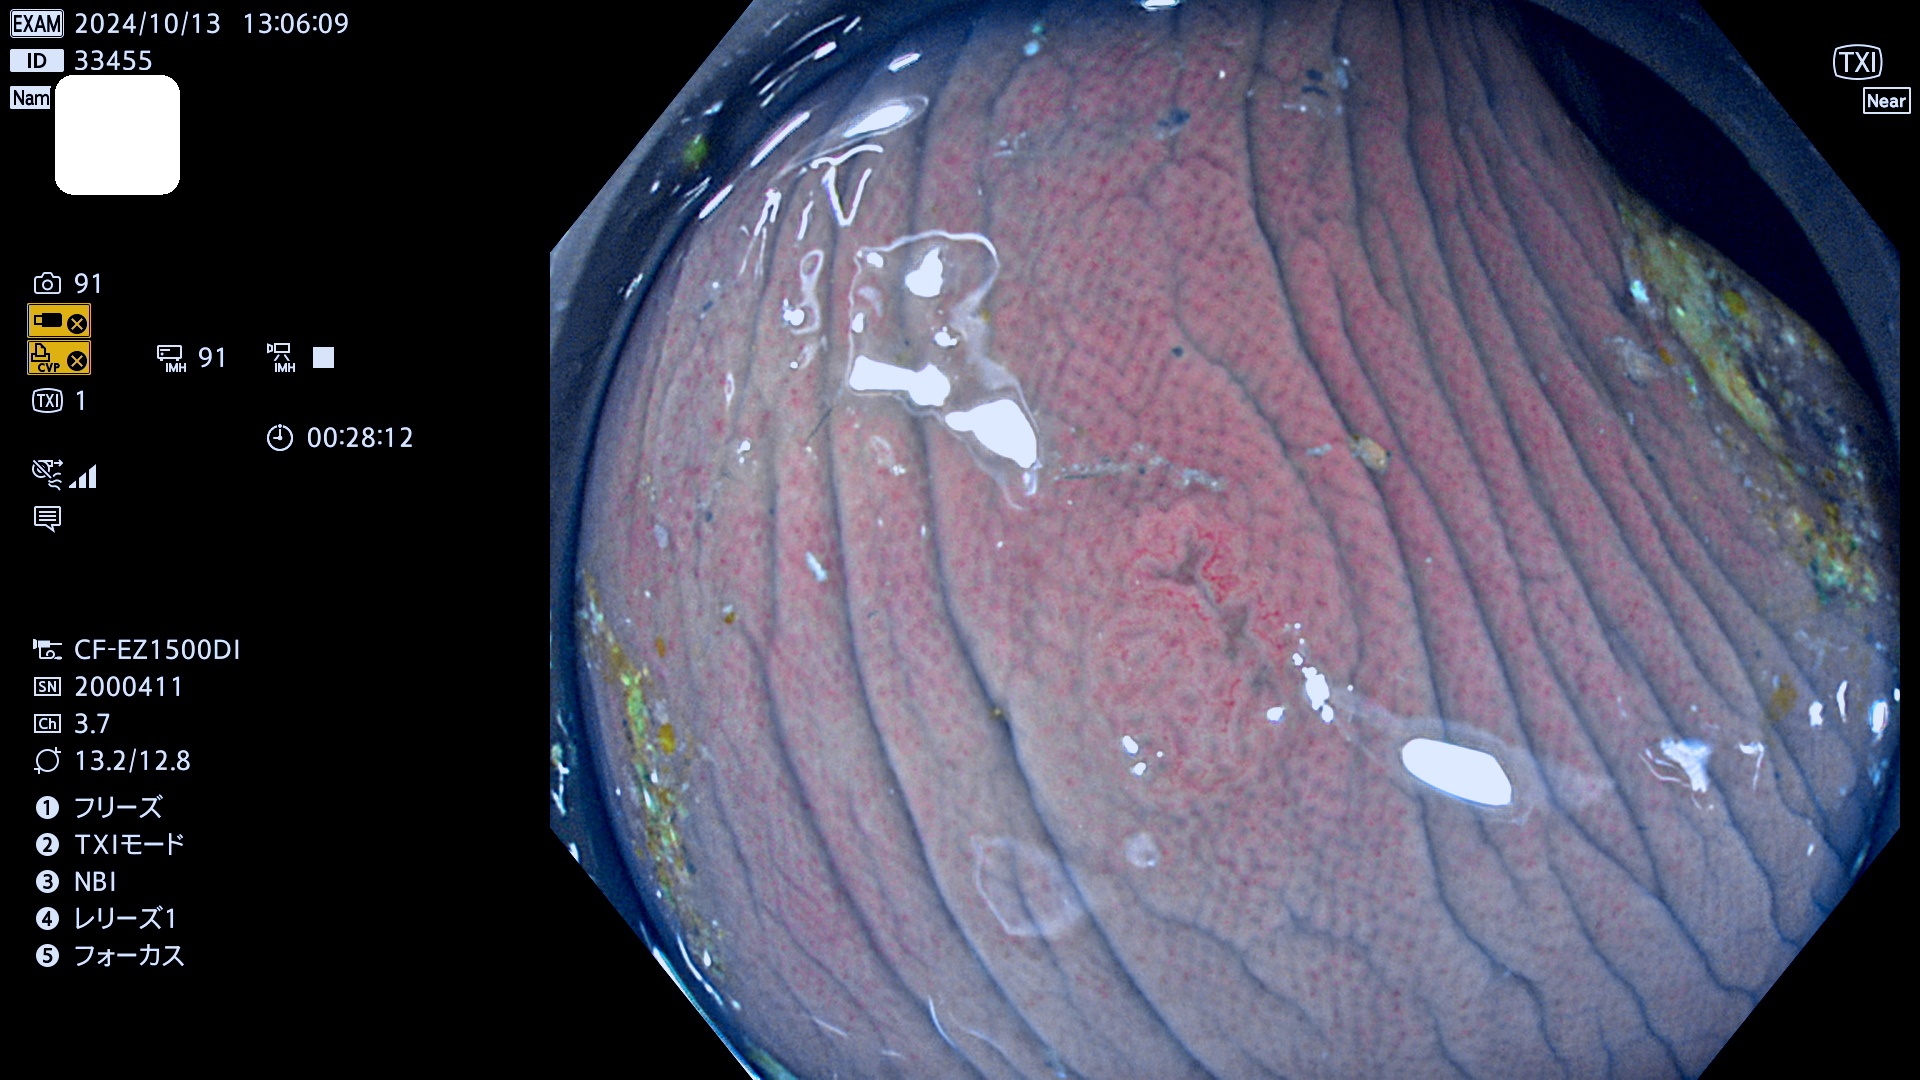

今週のUb、Uc型腺腫

完全に平坦な物をUb、陥凹している物をUcと呼びます。最も発見が難しく危険な病変です。

毎週の検査(木・金・土・日)に発見されたUb、Uc型・腺腫を、その週の日曜の夜にUPし1週間、提示します。

抽出の対象期間 2024年10月10日〜10月13日の4日間(48件の検査)7件 (7/48=14%)